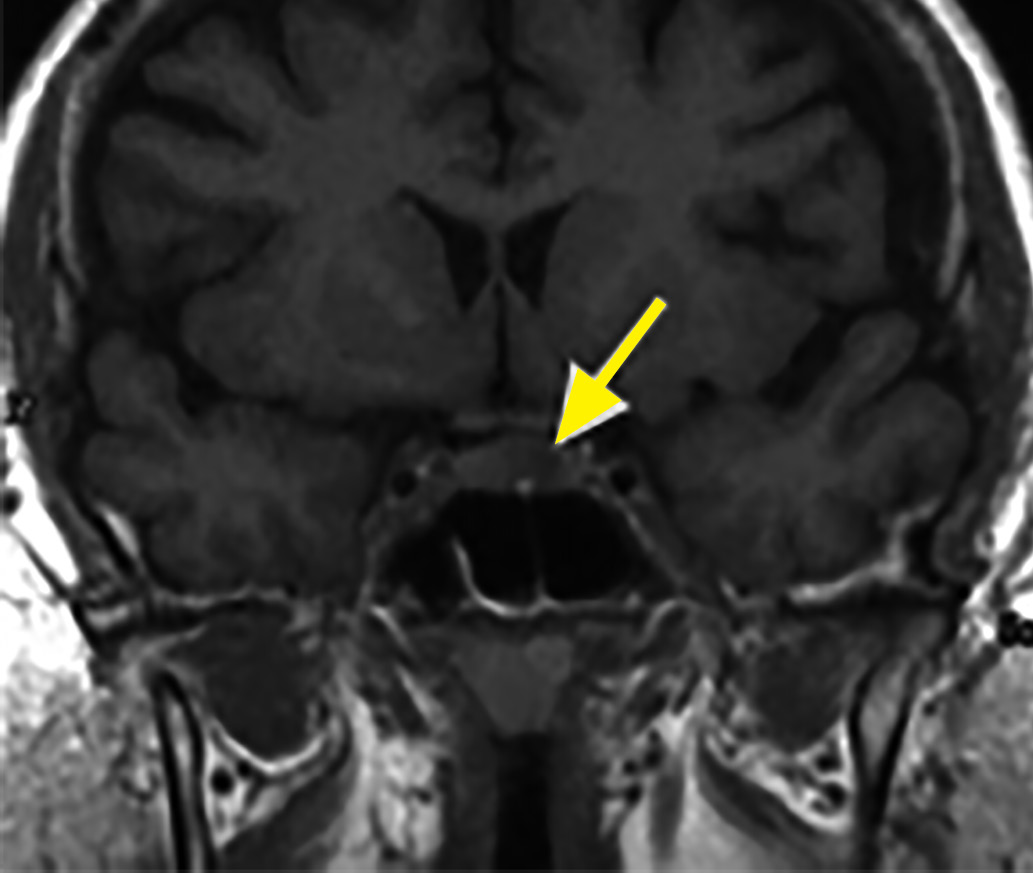

6. Figure 6. Endosellar corticotropinoma. Anterior T1-weighted MRI reveals a hypointense tumor (arrow). | |